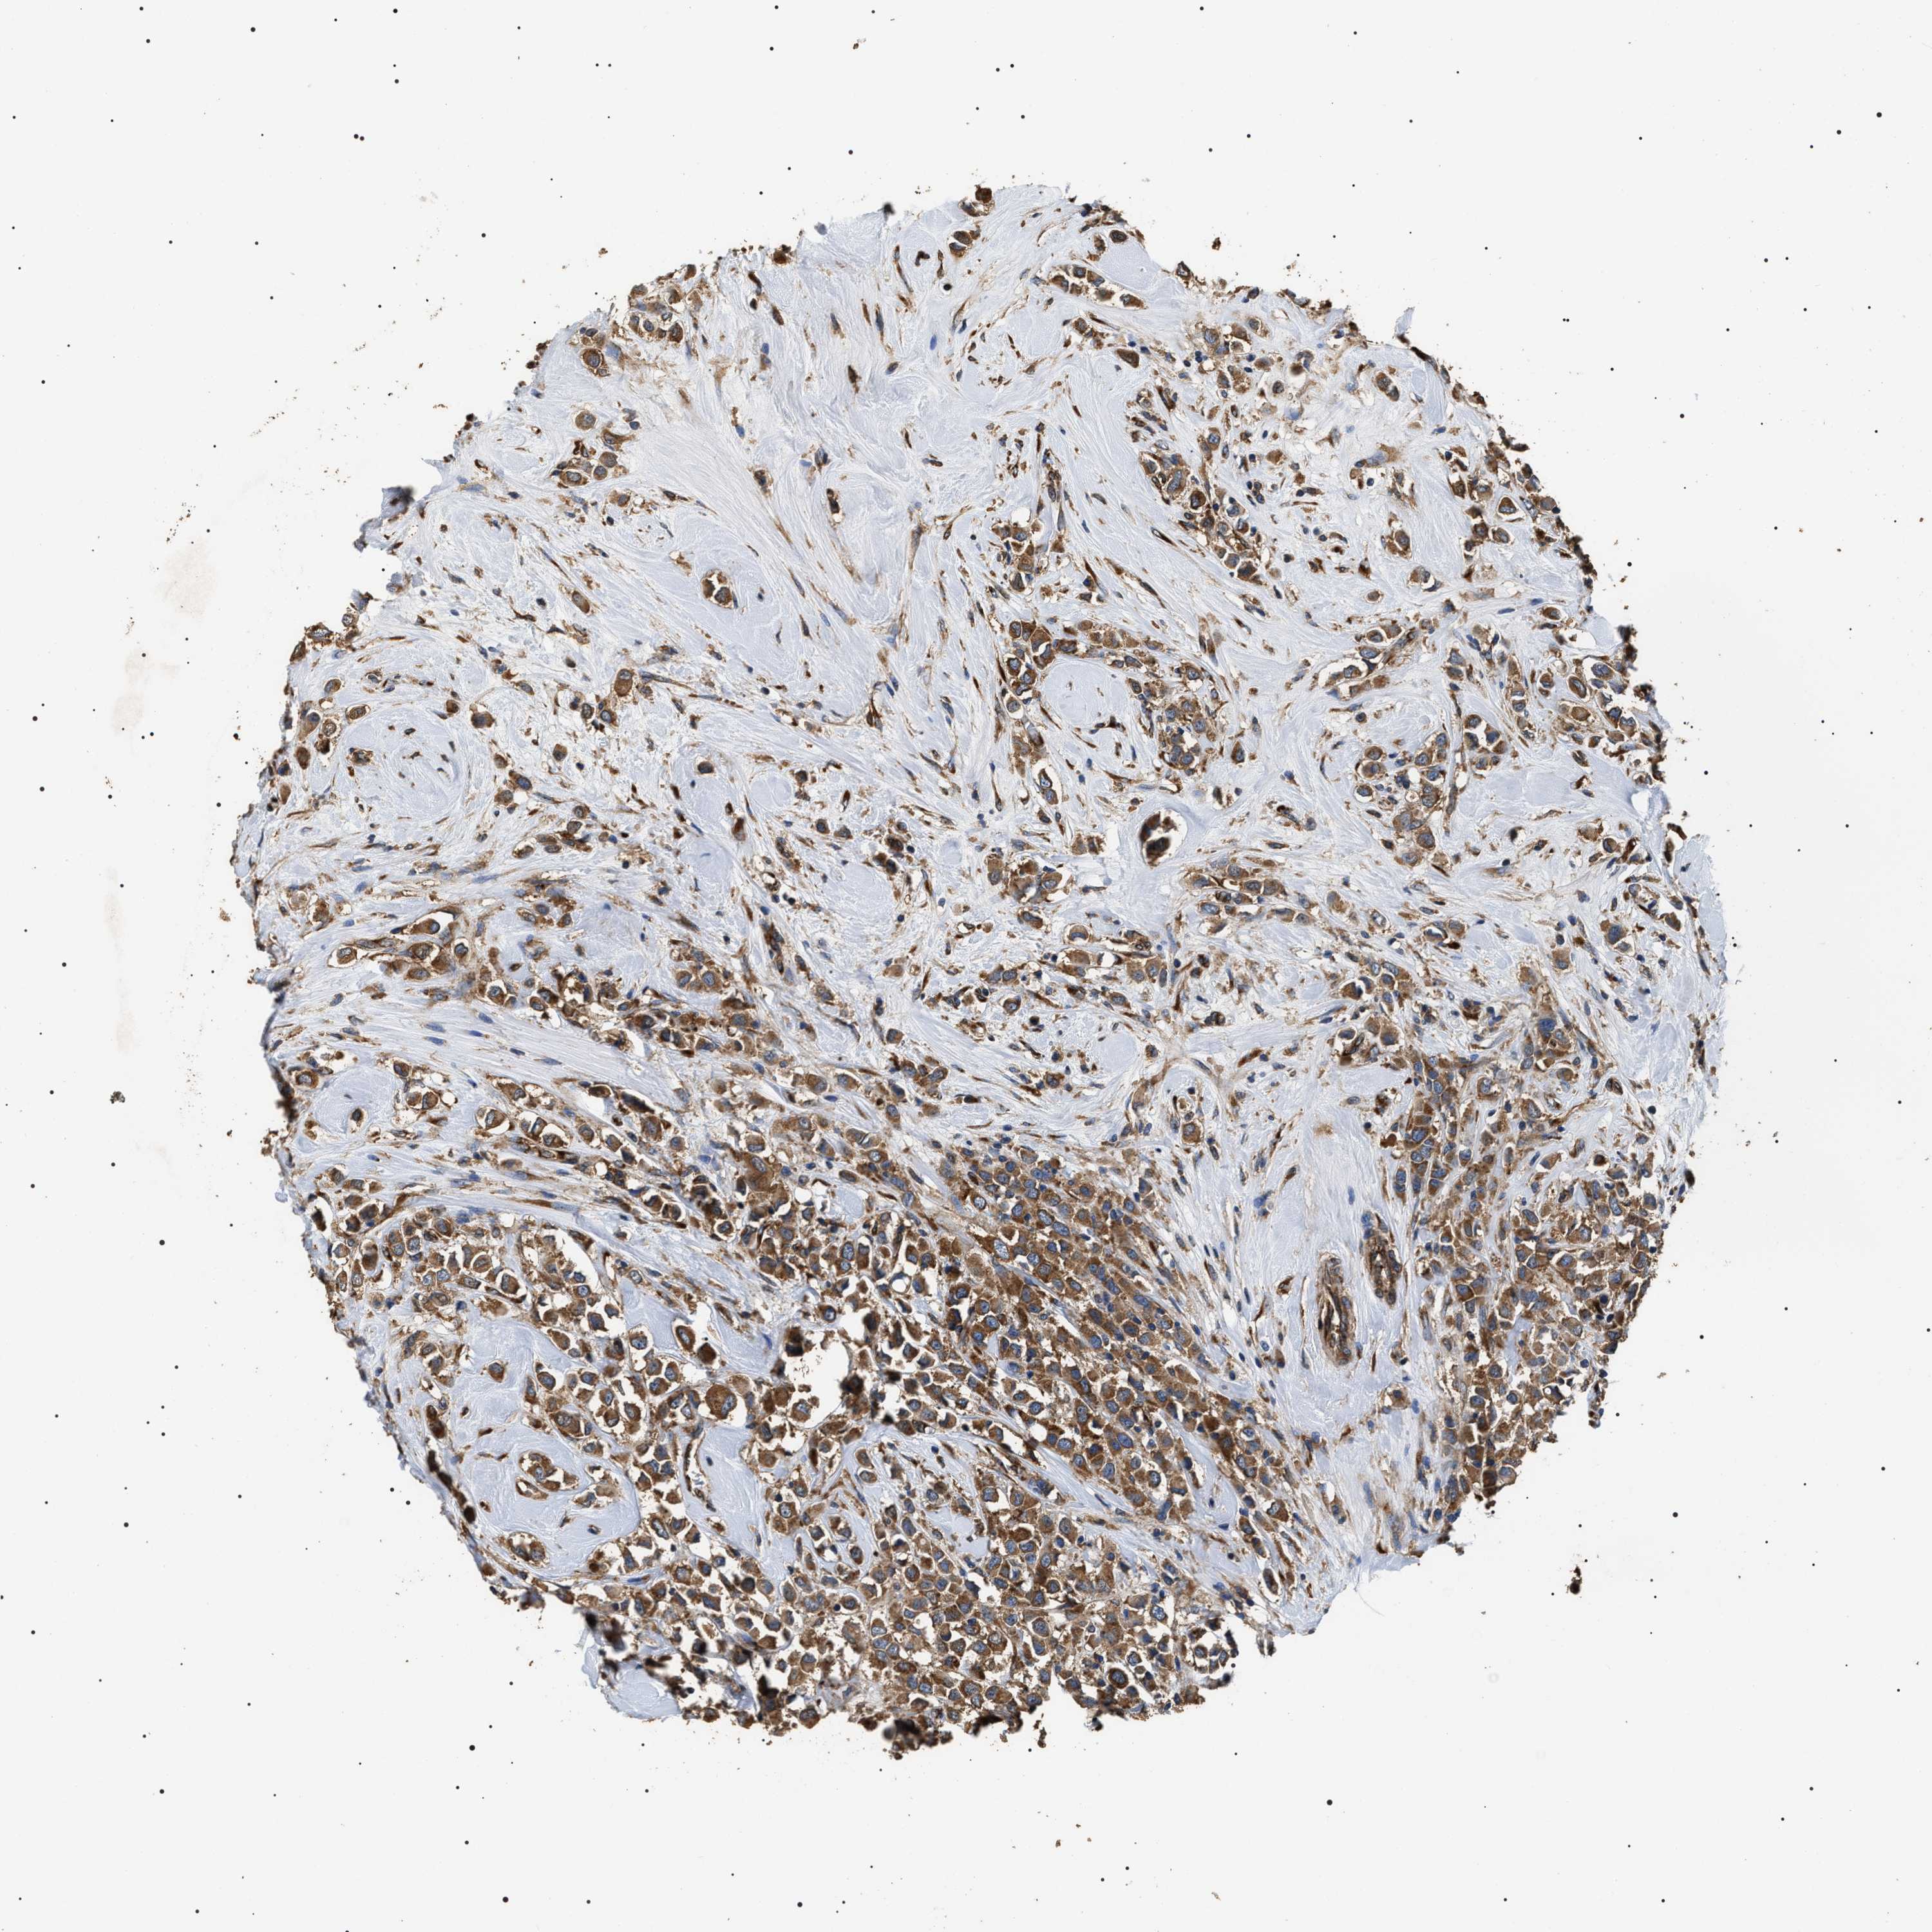

CANCER BREAST CANCER Show tissue menu

BRCA TCGA BRCA VALIDATION PROTEIN EXPRESSION